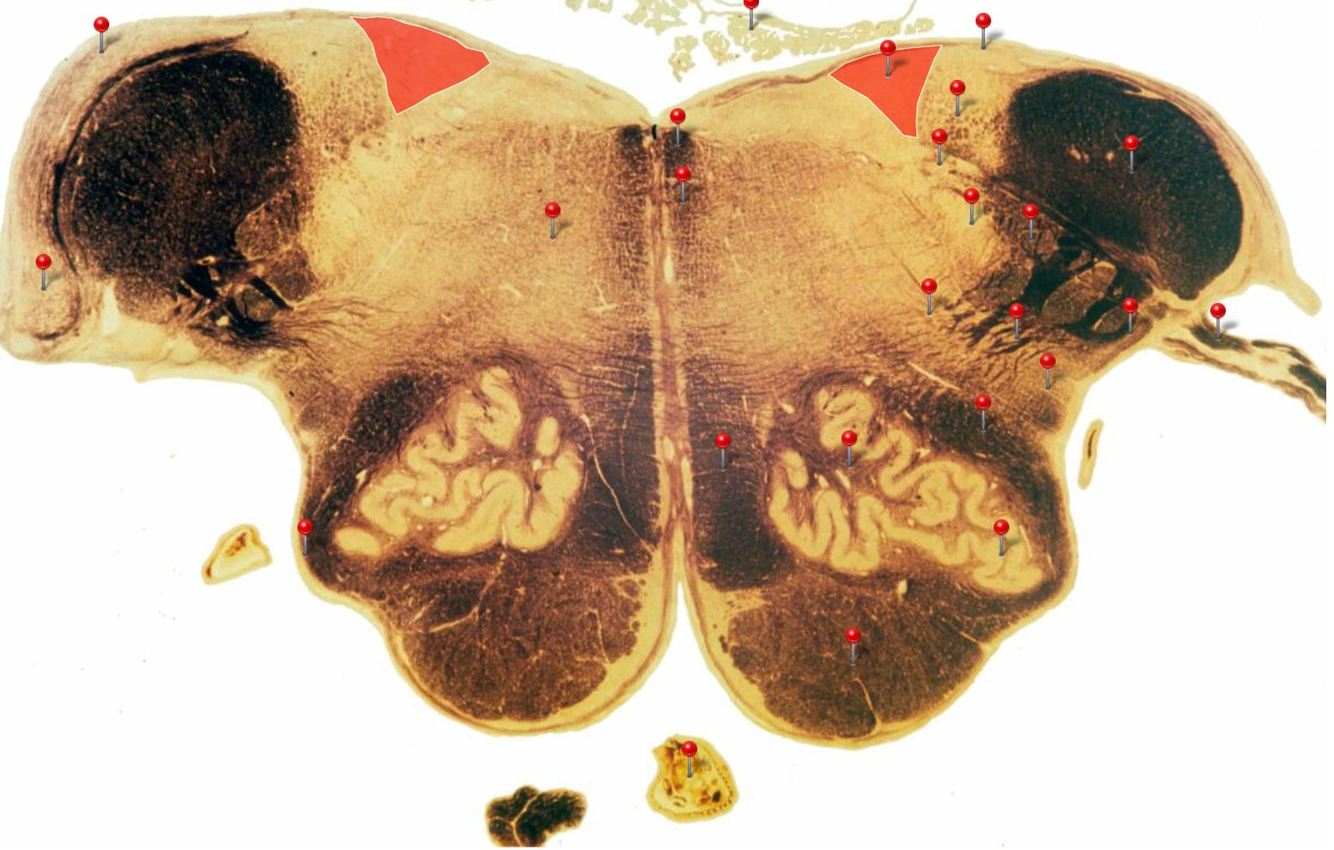

21

Q

A

Inferior Olivary Nucleus

Rostral Medulla

Plays an important role in the learning of new motor skills

22

Solitary Nucleus

Processes visceral afferent (GVA and SVA [taste]) inputs from CN VII, IX and X and relays them to the reticular formation and visceral efferent nuclei

23

Spinal Trigeminal Nuclei

Processes sensory inputs, particularly pain and temperature, from the head and neck and relays them to the ventral posteromedial nucleus of the thalamus

24

Inferior Vestibular Nucleus

Plays a role in the maintenance of balance and the coordination of eye and head movements

25

Medial Lemniscus Rostral Medulla Transmits sensations of **discriminative touch, vibration, proprioception** an **stereognosis** from the *gracile* and *cuneate nuclei* to the *ventral posterior nuclei of the thalamus*

26

Ventral Spinocerebellar Tract Rostral Medulla Provides feedback to the cerebellum concerning motor activity (including reflexes) in the lumbosacral levels of the spinal cord

27

Glossopharyngeal Nerve (CN IX) Rostral Medulla Transmits taste and tactile sensation from the posterior part of the tongue, pharynx and ear, and visceral sensation from the chemo- and baroreceptors of the carotid body and sinus (also supplies efferent fibres to the otic ganglion and stylopharyngeus m.)

28

Inferior Cerebellar Peduncle Rostral Medulla Formed by pathways passing in both directions between the medulla and cerebellum

29

Tectospinal Tract Rostral Medulla Function in humans not precisely determined; thought to mediate reflex movements of head in response to visual and perhaps auditory stimuli

30

Olivocerebellar Tract Rostral Medulla Transmits information from inferior olivary nucleus to the *contralateral* cerebellum, where it forms the **climbing fibres**

31

Lateral Vestibular Nucleus Rostral Medulla Contains cell bodies of the (lateral) vestibulospinal tract which regulates the activity of **axial** and **proximal** limb muscles in order to **maintain balance and posture**